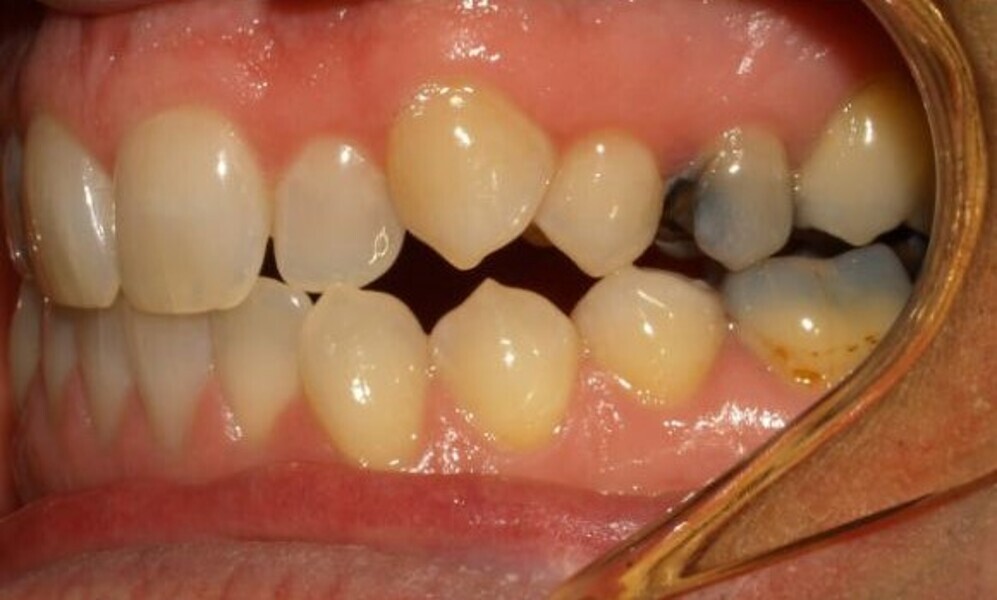

Aligners alone will fail because there are often significant skeletal components to Class II malocclusion, along with dental compensations, frequently making Class II a very difficult malocclusion to address with aligners alone (Figs. 16 & 17). Instead use fixed Class II correctors. An example is the Carriere Motion 3D Class II appliance (Henry Schein), utilised off maxillary canines or premolars back to first or second molars. Again, other movements can be happening in other areas of the mouth while the Class II correction is occurring, including maxillary canine canine alignment, if desired (Figs. 18 & 19).

The outcome is concomitant Class II correction while the aligners are aligning elsewhere, toward the fastest, most assured and synergistic antero-posterior correction possible.

Fig. 18a: Class II malocclusion requiring fixed appliance treatment. (a) Lateral view. (b) Occlusal view.

Fig. 18b: Class II malocclusion requiring fixed appliance treatment. (a) Lateral view. (b) Occlusal view.